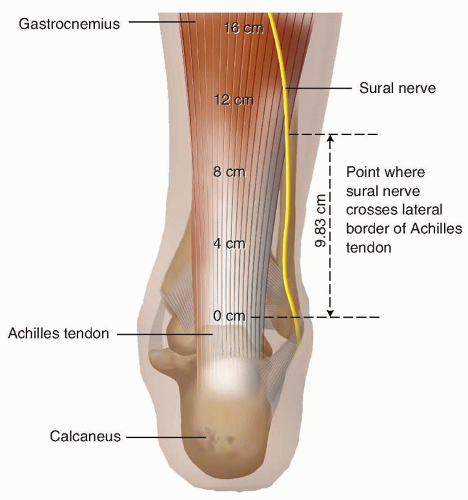

Transverse section of the Achilles tendon (midportion) region. Relation …